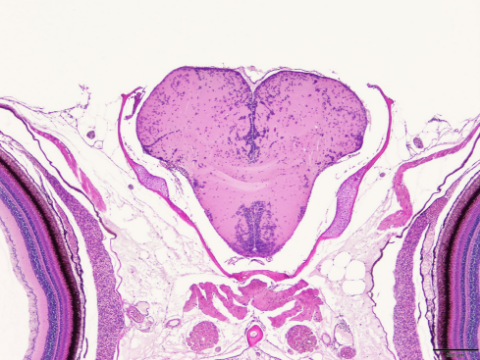

生殖腺の熟度判定あるいは病理組織の観察において組織切片標本の作製は有効な方法ですが、標本を仕上げるまでの煩雑な処理過程はかなりの時間を要していまします。マリノリサーチでは、わずかな試料からでも、ご要望に合った組織切片標本を作製いたします。

組織切片標本作製の写真

生殖腺片切片標本による成熟度判定

6~8μmの厚さの切片標本を切り出し、エオシン・ヘマトキシリン二重染色をおこないます。ご要望があれば、すべての標本の写真撮影をおこない成熟段階を標記いたします。成熟度の判定が目的でしたら、ホルマリン固定の状態でお送り頂ければ結構です。